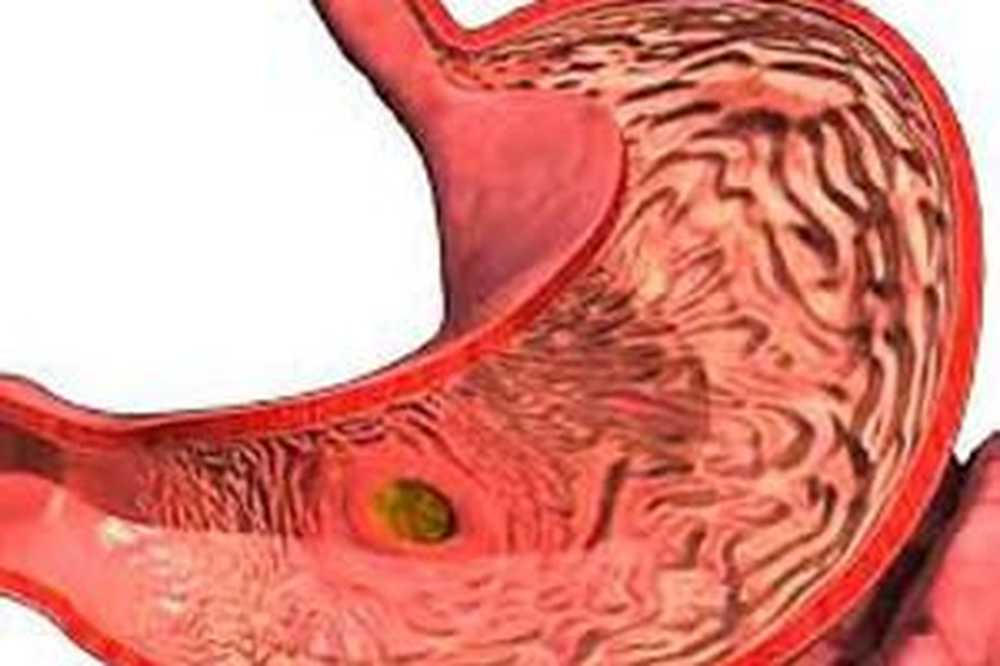

Информация и фотографии о хроническом гастрите и дуодените